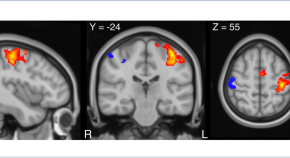

Noninvasive brain stimulation (NIBS) is a promising approach for facilitating recovery of motor function after stroke, but trials assessing its efficacy have provided contradictory results. Di Pino and colleagues propose a unified 'bimodal balance–recovery model' for stroke recovery that takes into account the individual residual structural reserve and could aid tailoring of treatment for individual patients, thereby increasing the efficacy of NIBS in stroke rehabilitation.